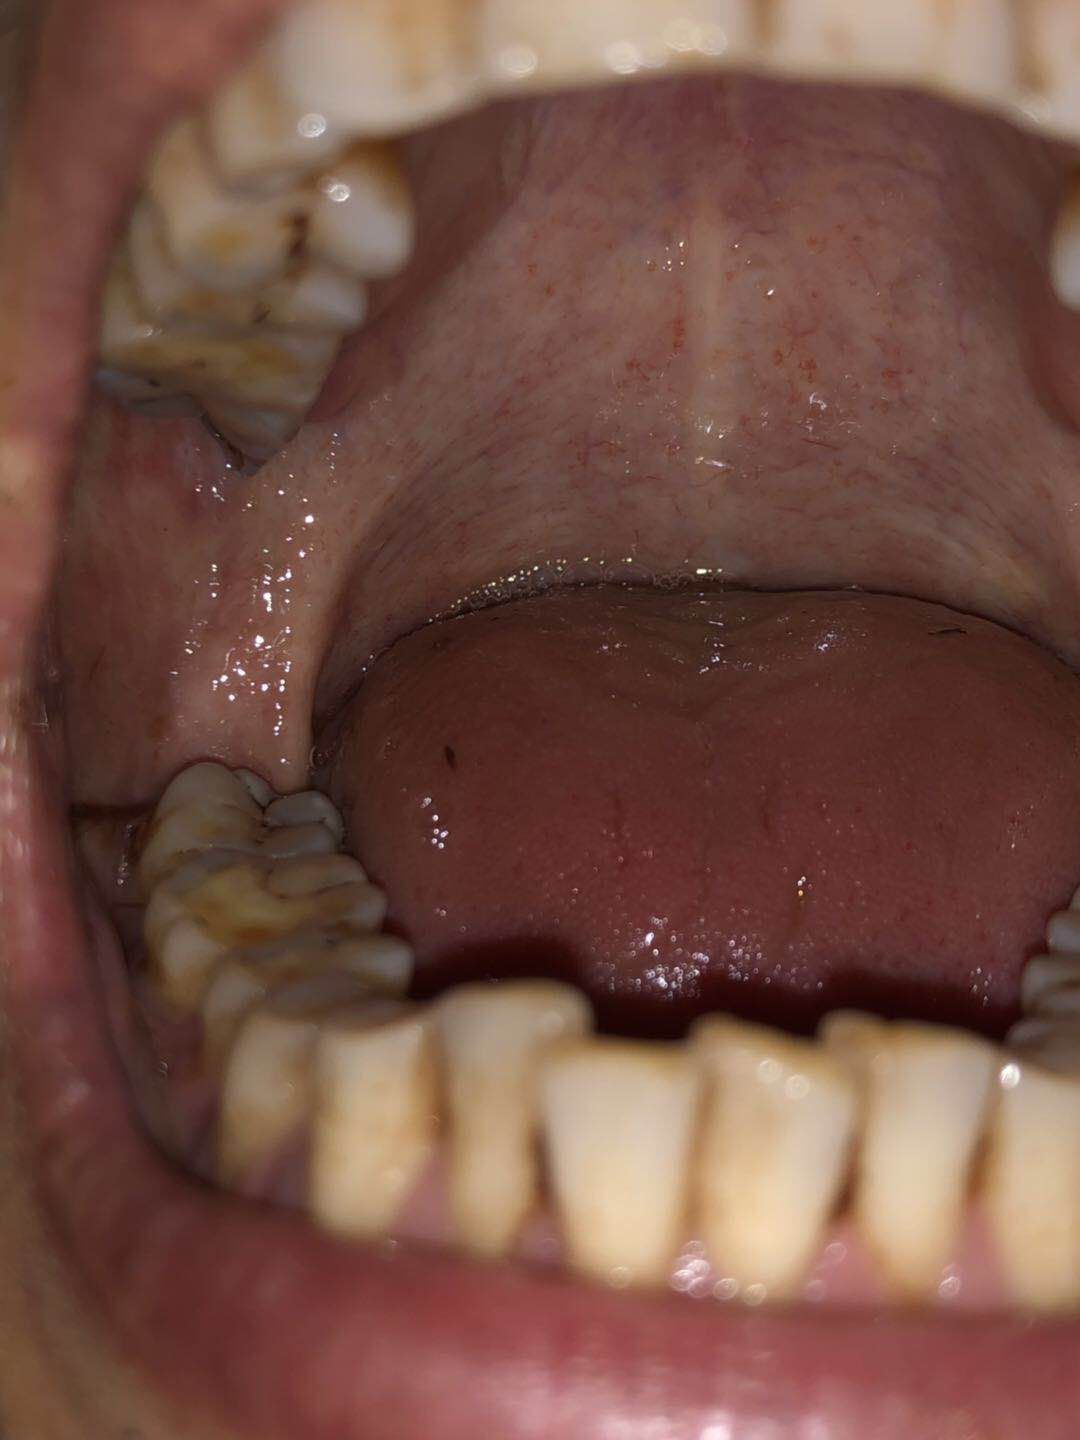

口腔已纤维化内壁不平有痛感

图片尺寸648x1152